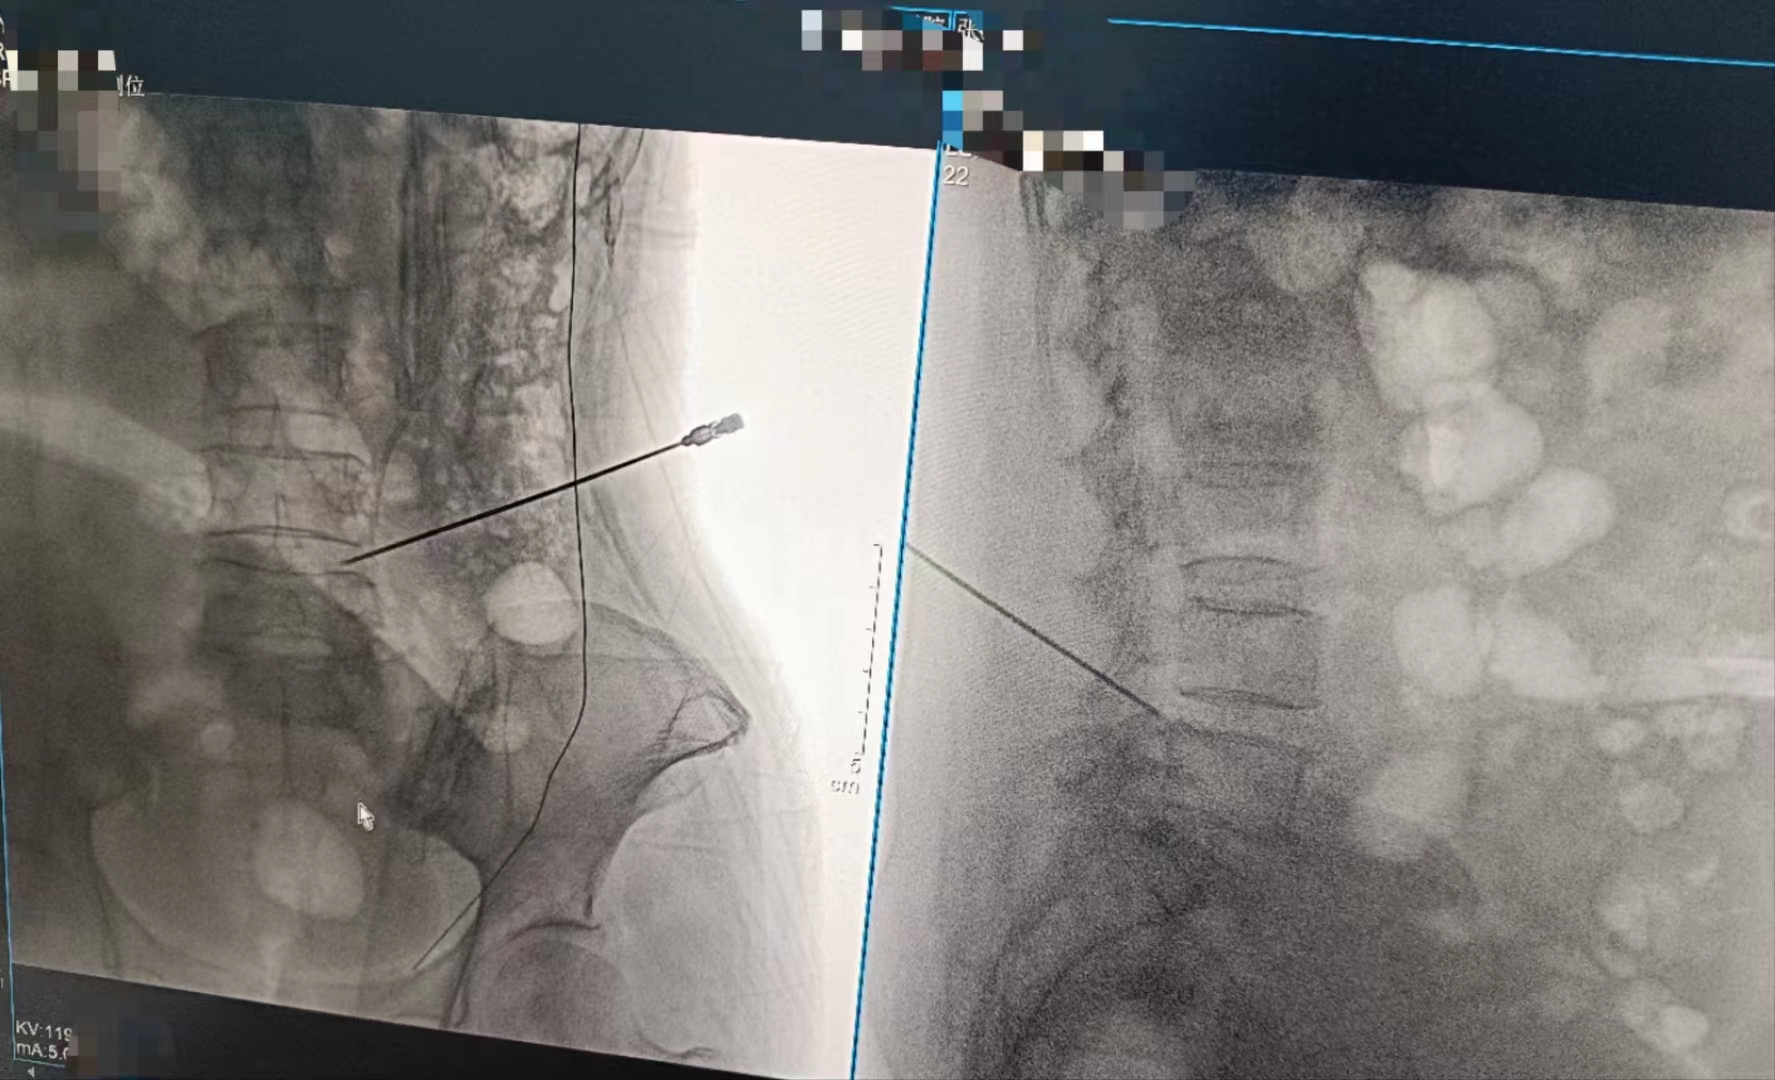

當(dāng)設(shè)備啟動,那束柔和的X射線穿過患者的身體,捕捉下每一個細(xì)微的影像。那一刻,時間仿佛凝固,所有的目光都聚焦在那塊屏幕上。那里,生命的紋理清晰可見,疾病的陰影無處遁形。